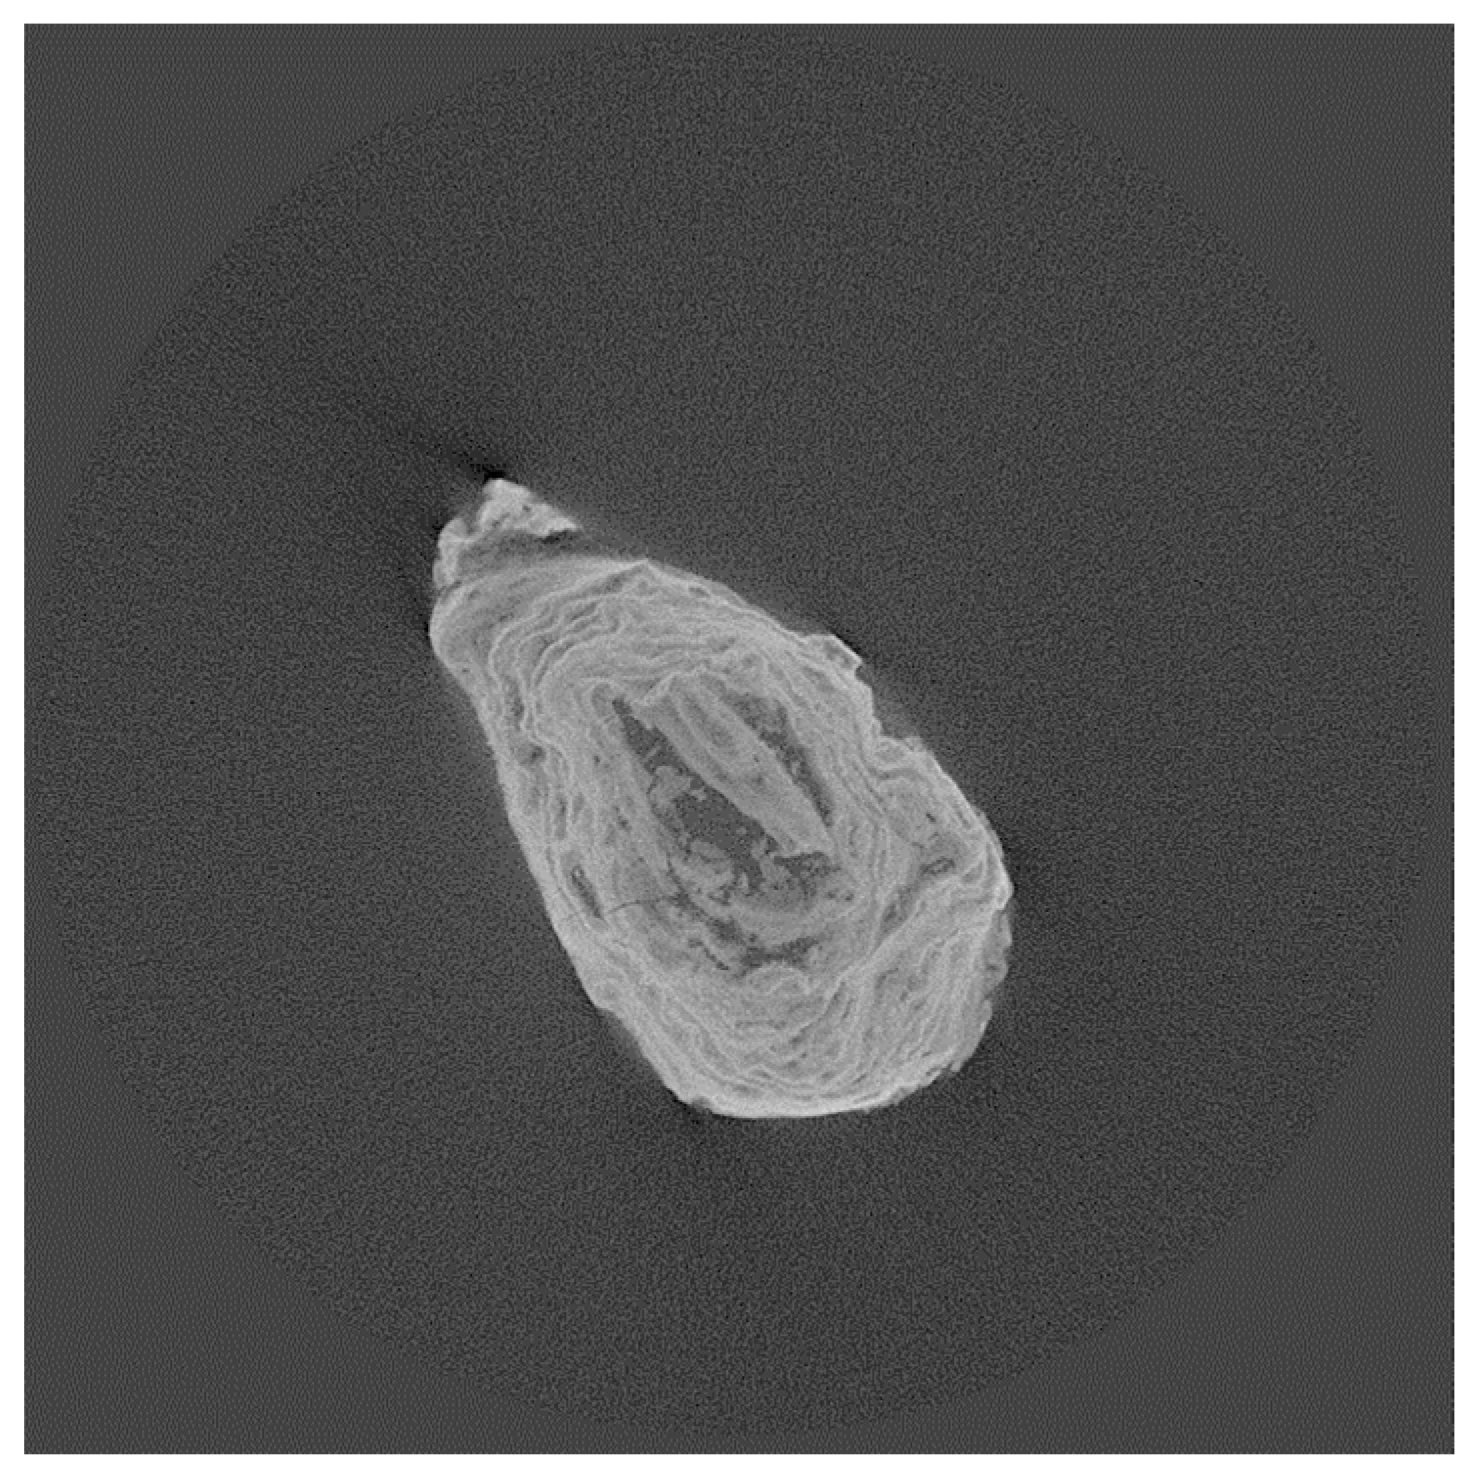

3.1.1. Calcium Oxalate Kidney Stones

Analysis of Kidney Stones M1, M3, M5, M6, and F6

| Calcium kidney stones | M1, M3, M5, M6, F6 | Mostly calcium oxalate (whewellite (w), weddellite (wd)) |